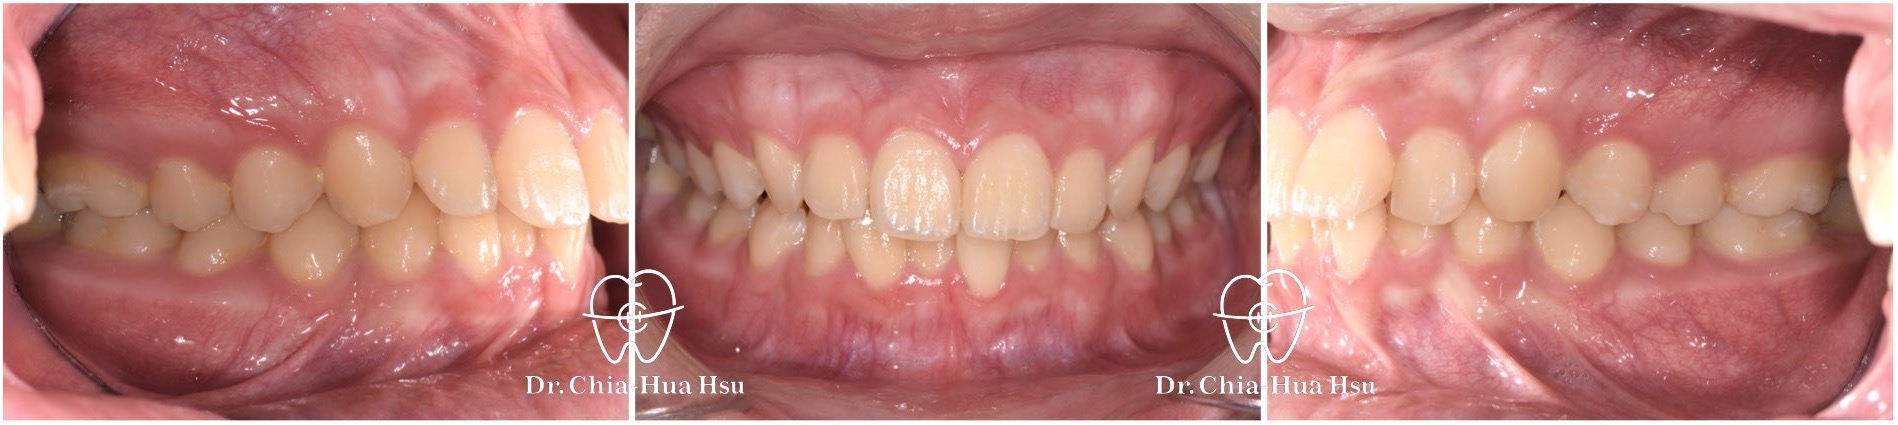

治療前

治療後